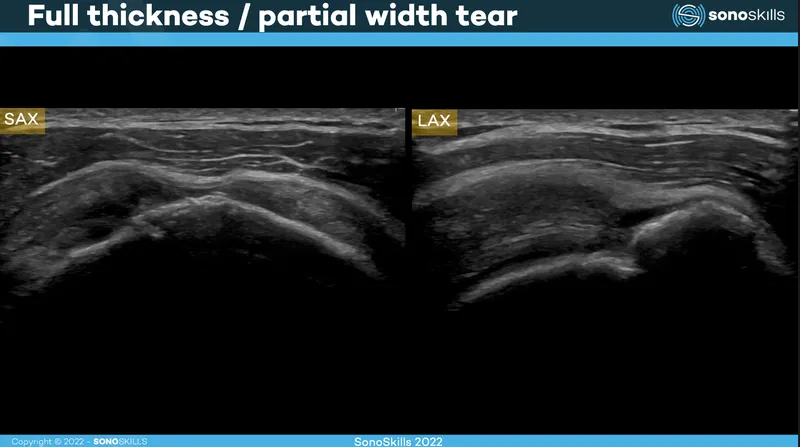

- Tendon/Ligament Injury: Assesses tears (partial/full thickness), tendinosis, enthesopathy, sprains.

- Look for fiber discontinuity, hypoechogenicity, neovascularity.